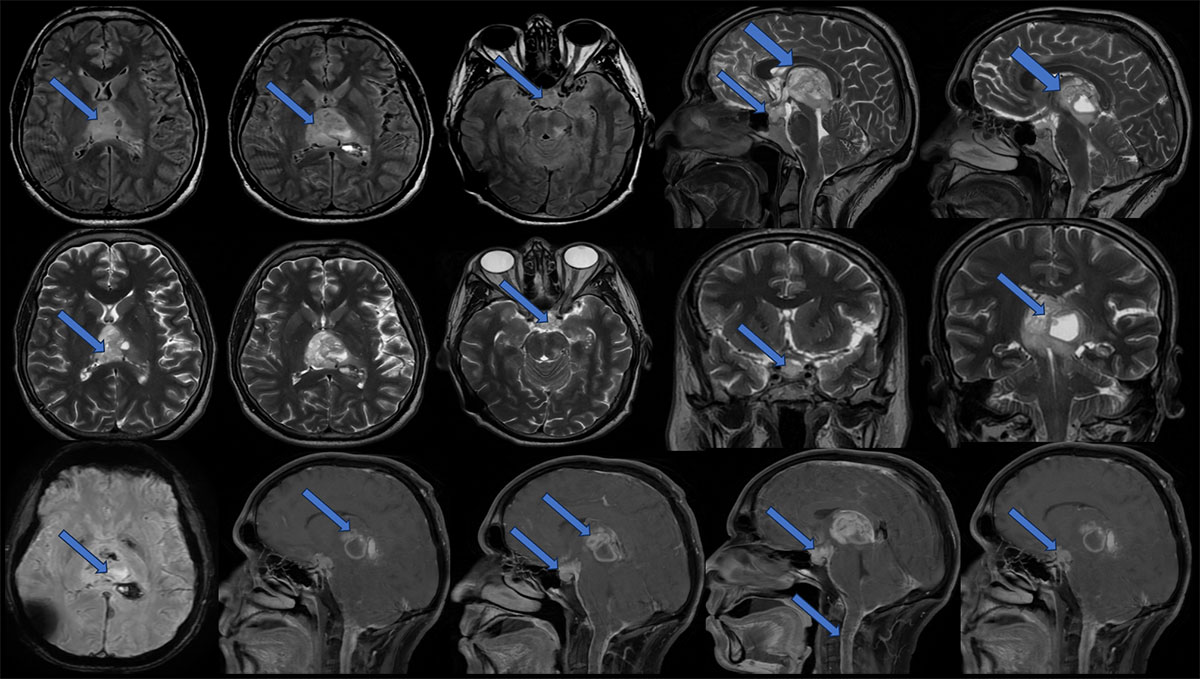

MRI:

- Heterogeneous, multiloculated solid-cystic lesion with calcifications and haemorrhage in pineal region causing mass effect of brainstem, the solid component shows intense enhancement and the cystic areas show peripheral enhancement.

- Similar solid lesion seen in sellar-suprasellar region, shows intense contrast enhancement.

- Multifocal areas of nodular and smooth leptomeningeal enhancement predominantly along the cerebral hemispheres (L>R).

- There is leptomeningeal enhancement along the visualised cervical cord – leptomeningeal drop metastasis.